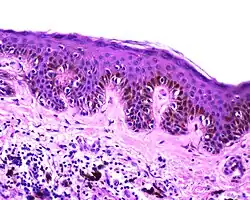

| Dysplastic nevus | Usually a compound nevus with cellular and architectural dysplasia. Like typical moles, dysplastic nevi can be flat or raised. While they vary in size, dysplastic nevi are typically larger than normal moles and tend to have irregular borders and irregular coloration. Hence, they resemble melanoma, appear worrisome, and are often removed to clarify the diagnosis. Dysplastic nevi are markers of risk when they are numerous, such as in people with dysplastic nevus syndrome. According to the National Institute of Health (NIH), doctors believe that, when part of a series or syndrome of multiple moles, dysplastic nevi are more likely than ordinary moles to develop into the most virulent type of skin cancer called melanoma.[19] | ![]() In this case, the central portion is a complex papule, and the periphery is macular, irregular, indistinct and slightly pink. |

Characteristic rete ridge bridging, shouldering, and lamellar fibrosis. H&E stain.